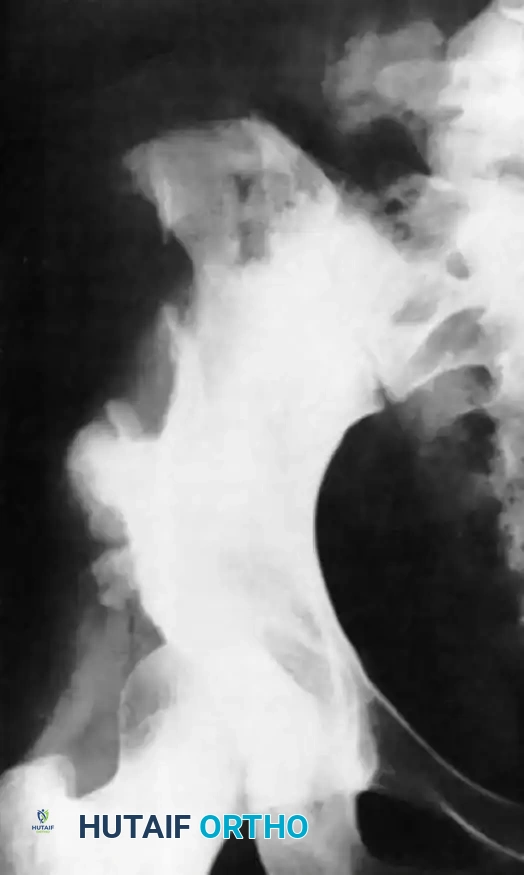

Intraoperative Radiography and Fluoroscopy

Orthopaedic surgery relies heavily on real-time intraoperative imaging to assess fracture reduction, implant trajectory, and joint congruency. The integration of portable radiographs and C-arm image intensifiers requires strict adherence to aseptic technique and radiation safety.

Aseptic Technique for Imaging

When unsterile radiograph cassettes are introduced into the sterile field, they must be isolated. The cassette is placed inside a sterile double pillowcase or a specialized sterile plastic bag, folded to maintain exterior sterility, and covered with a large sterile towel.

For continuous fluoroscopy, the C-arm must be meticulously draped.

The draping process must allow for free rotation of the C-arm from anteroposterior (AP) to lateral planes without compromising the sterile field. The surgeon and scrub nurse must coordinate the movement of the machine, ensuring the unsterile base never breaches the sterile boundaries.